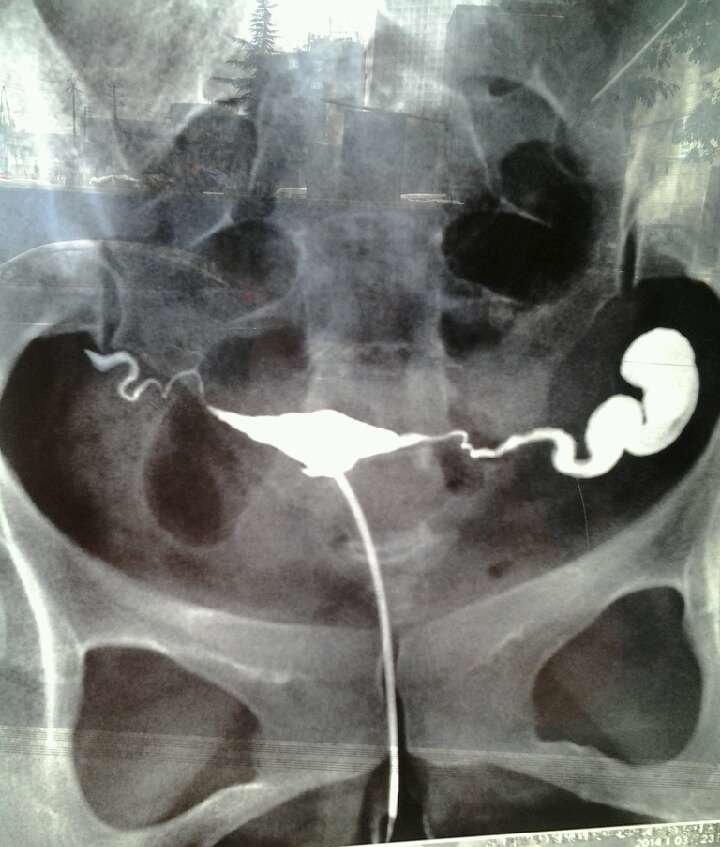

求讲解输卵管造影图片

我做的碘油造影,医生说让我做腹腔镜。我考虑到会留疤痕之类的,我输卵管这种情况是不是必须做腹腔镜啊?是不是真的全部堵上了??第二张是第二天重拍的。

病情分析: 这情况建议就近到三甲医院进行宫腔镜联合术来治疗比较好,术后可以顺利怀孕的。 指导意见: 也可试试用中草药的,双花、生地、黄芩、木香、甘草、当归、川芎、白芍、川楝子、元胡、芡实、薏米、黄芪。一般治疗1~3个疗程。